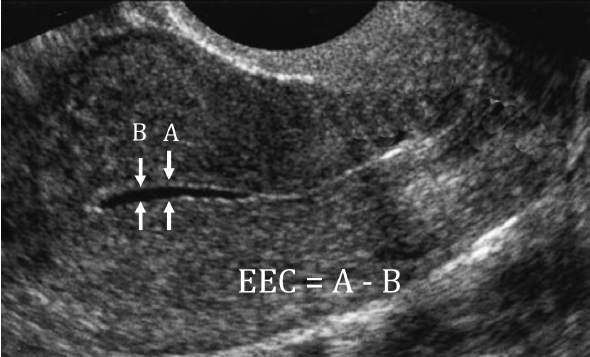

子宫内膜增生

子宫内膜不典型增生,意味着子宫内膜细胞生长异常,具有癌变风险。但“风险”不等于“癌症”。对于有强烈生育意愿的年轻女性,医学的首要原则是在安全的前提下,尝试保留子宫、逆转内膜。

2. 定期宫腔镜复查:这是金标准。每3个月左右,医生需要通过宫腔镜直视下取活检,病理评估内膜是否已逆转为正常。只有病理报告确认内膜“无异常”后,才能考虑进入备孕阶段。